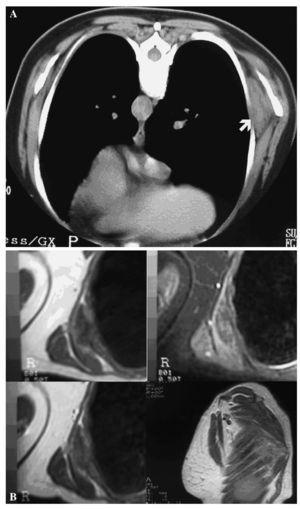

Figura 1.Ecografía de región subescapular en una mujer de 49 años asintomática que únicamente refería una tumoración en la pared torácica posterior derecha. Realizada en prono y abducción.

Se distinguen 7 estratos: piel (1); grasa subcutánea (2); fascia superficial con grasa (3); músculos extrínsecos de la espalda (4); fascia de la parrilla costal (5); músculos intercostales y arcos costales (6); superficie pulmonar (7). En la quinta capa se observa una masa con patrón estriado y ecogenicidad similar al músculo, alternando con otras bandas hipoecoicas de grasa de contorno globuloso, rodeada de grasa y con pobre diferenciación de los músculos adyacentes, sin alteraciones óseas y sin flujo significativo con doppler color.